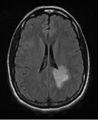

- MRI

- Multiple lesions in supratentorial white matter, paraventricular area, spinal cord